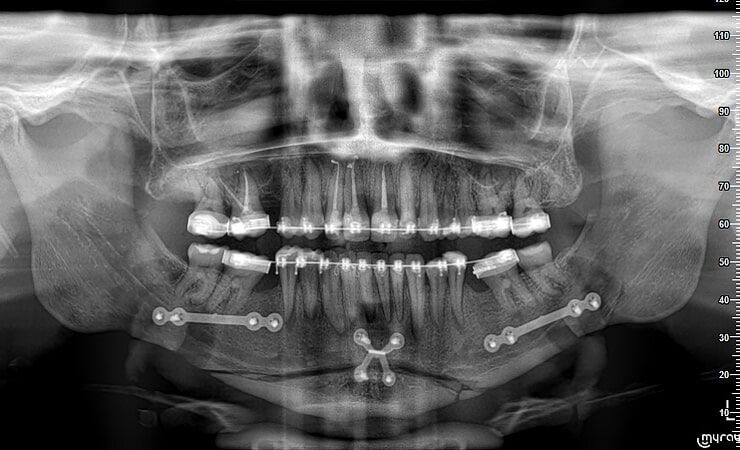

MENTON RÉTRACTÉ

MALOCCLUSION

Le traitement adopté fut la chirurgie d'avancement de la mâchoire et la génioplastie.